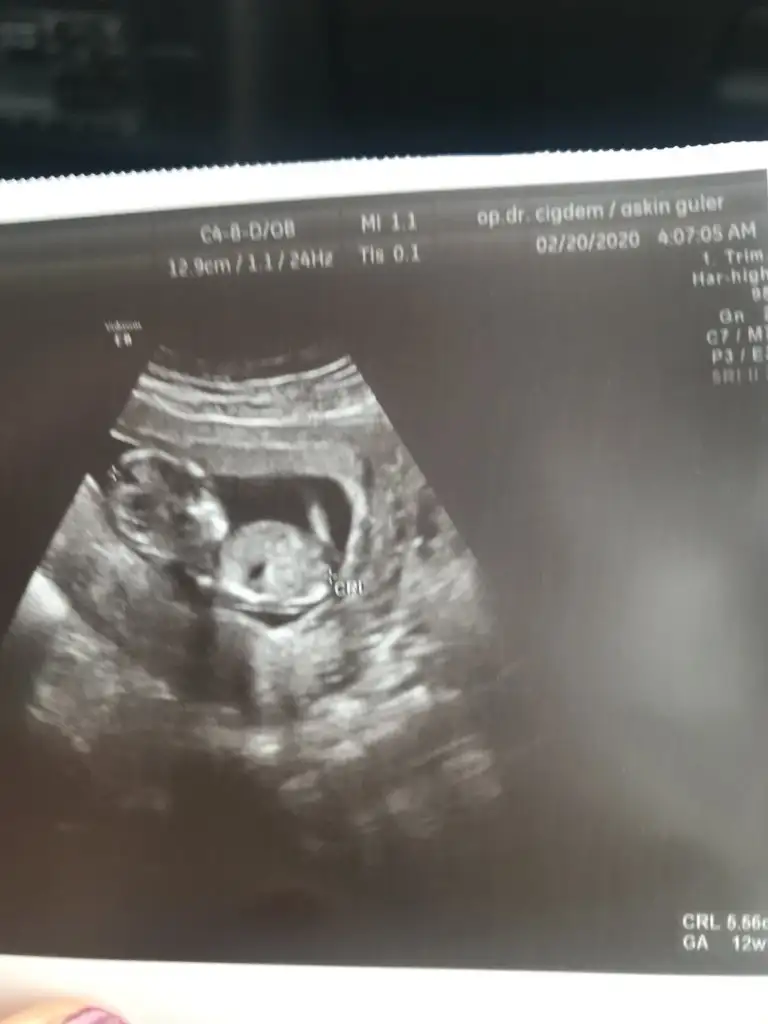

Dr + tam nuba denk getirmiş başka usg varmı12+4 banada yorumlarmisijizIkra meyra

Bu göre kız ama tutmayabilir tekrar usg olursa paylaşın .usteki 12+3 usg de kafa yapısı kız gibi ama nub göremiyorum .13+ usg olursa paylaşırsınızBaska yok![]()

Hemen göndereyim olması lazımdıBunlar var birde videodan aldığım bir görüntü vardıEki Görüntüle 2596225 Eki Görüntüle 2596225 Eki Görüntüle 2596226 Eki Görüntüle 2596227